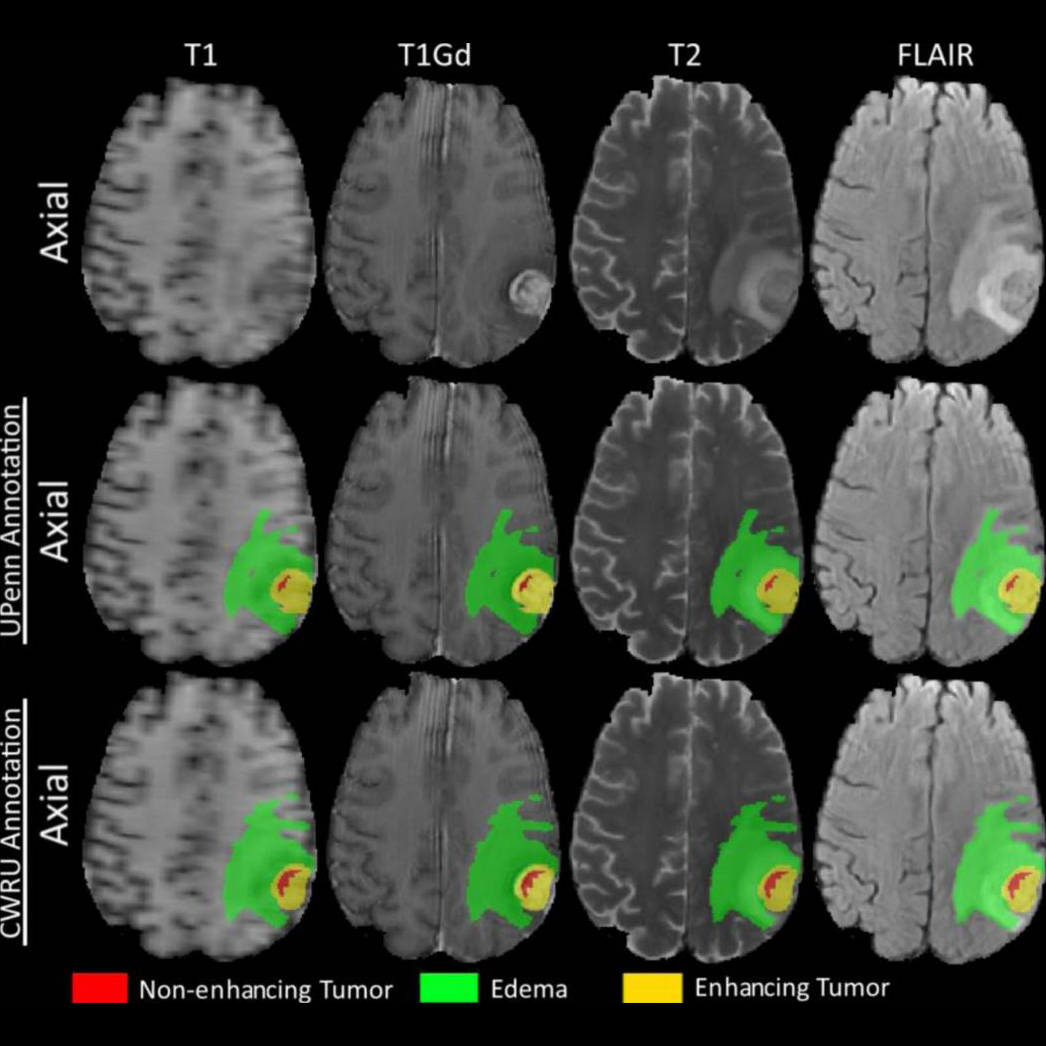

Reproducibility analysis of multi-institutional paired expert annotations and radiomic features of the Ivy Glioblastoma Atlas Project (Ivy GAP) dataset

Sarthak Pati, Ruchika Verma, Hamed Akbari, and 8 more authors

Medical physics, 2020